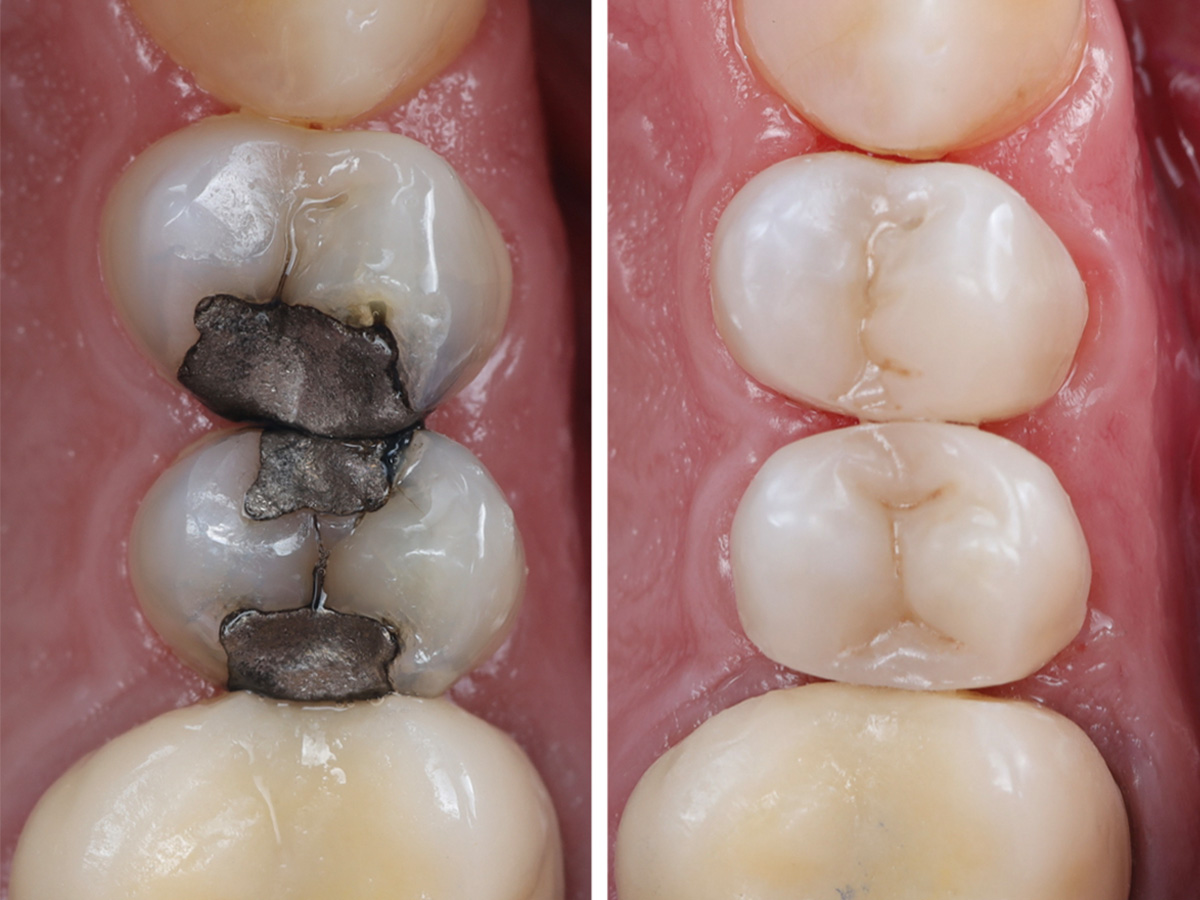

Vorher/Nachher